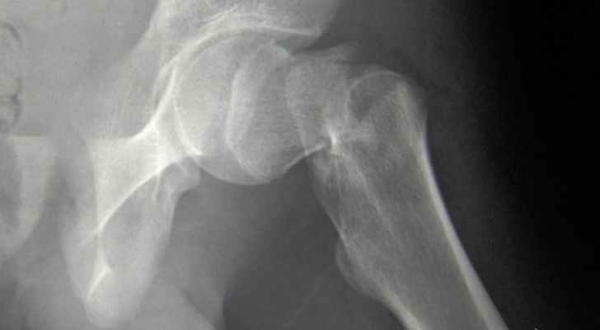

كسور الورك

كما وجد الباحثون أن النساء اللواتي لديهن مستويات عالية نسبياً من التوتر والقلق كن أكثر عرضة لخطر الإصابة بكسور عظمية بنسبة 4% خلال فترة 10 سنوات.

وكانت كسور الورك أكثر شيوعاً بنسبة 3% في المجموعة التي تعاني من القلق، واللاتي كن يملن بشكل عام إلى الحصول على درجات كثافة أقل للعظام.